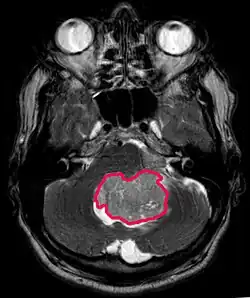

MRI toont meestal een enorme contrastverhogende laesie waarbij het cerebellum betrokken is. Zoals hierboven vermeld, heeft medulloblastoom een hoge neiging om lokaal de leptomeningen te infiltreren en zich ook door de subarachnoïdale ruimte te verspreiden, waarbij de ventrikels, cerebrale convexiteit en leptomeningeale oppervlakken van de wervelkolom betrokken zijn. Daarom is het noodzakelijk om de gehele craniospinale as in resonantie te brengen.

Deze tumor is typerend voor de achterste fossa, waar hij is gelokaliseerd in beide hemisferen van het cerebellum of in de cerebellaire vermis. Omdat het invasief en snelgroeiend is, verspreidt het zich gewoonlijk naar andere delen van het centrale zenuwstelsel (CZS) via het CSF en kan het de bodem van het nabijgelegen vierde ventrikel en de hersenvliezen infiltreren. Meer zelden kunnen aanvullende CZS-metastasen optreden. Wanneer de maligniteit optreedt, omvatten de symptomen verlies van evenwicht, coördinatiestoornissen, diplopie, dysartrie en als gevolg van betrokkenheid van de vierde ventrikel, wat vaak resulteert in obstructieve hydrocephalus, hoofdpijn, misselijkheid en braken, en onstabiel lopen.

Aan -MRI toont een intracraniële tumor als een massieve laesie die na gebruik van het contrastmiddel meer luminescent kan worden. Er is echter altijd een signaalafwijking in -Magnetic resonance imaging, die de aanwezigheid van neoplasie of vasogeen oedeem aangeeft. Gewoonlijk is verhoogde luminescentie (contrastversterking) indicatief voor een tumor met een hogere graad van maligniteit. Kenmerkend voor glioblastoom is een contrastring, waarbij het lichtgevende deel overeenkomt met het vitale deel van de kwaadaardige tumor en het donkerdere -hypointens gebied dat overeenkomt met weefselnecrose.